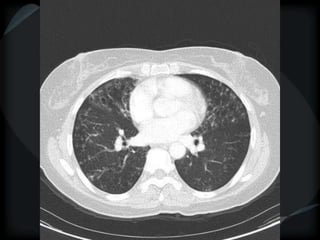

Tree-in-Bud Appearance

Bronchiolitis

Rare- tumor cell emboli – intralobular artery

Tree-in-bud / MAI

bronchiolar

Bronchiolitis - MTB

Subacute HP

bronch / peribronch / gg

RBILD

Avium / DPB